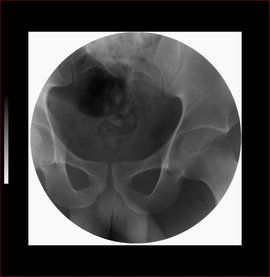

X線檢查對隱性脊柱裂的發現和脊柱外傷有助。

8.隱性脊柱裂

發病年齡早,夜間遺尿,幼年尿床時間長是其特點。